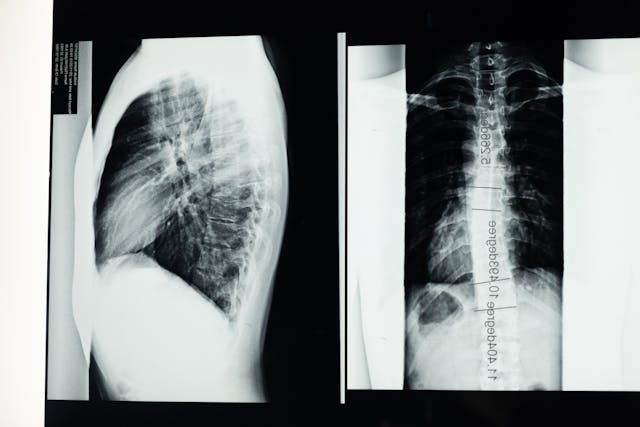

Bolesti zad patří mezi nejčastější bolesti vůbec. Koho by dnes nebolela záda? Původcem bolestí zad může být třeba skolióza, která může být vrozená i získaná. Ideální je, když se na skoliózu přijde co nejdříve v dětském věku. Pokud se zjistí až v dospělosti, už je léčba složitější, ale rozhodně ne nemožná. Vyléčit skoliózu je samozřejmě možné, ale chce to včas začít řešit, z čeho vlastně vznikla. Často ani člověk neví, že skoliózu má, ale bolesti zad ho donutí zajít si k lékaři a zjistit jejich příčinu. Skolióza je problematická především v tom, že neustále bolí. Bolesti mohou být natolik velké, že pacientovi znesnadňují život. Omezuje i běžné denní aktivity, což je rozhodně nepříjemné.